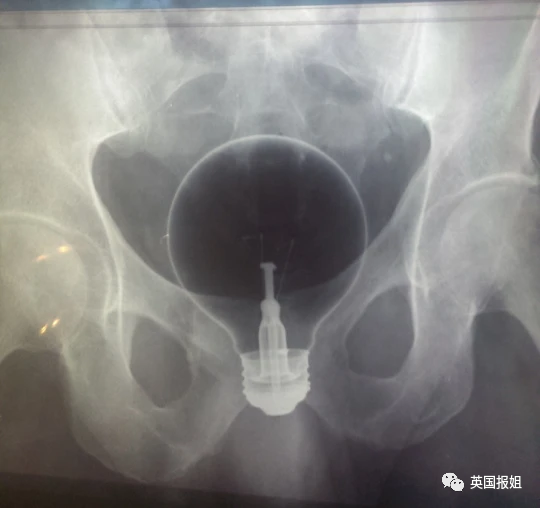

比如人人都知道放进去就取不出来的灯泡:

甚至还发明出了灯泡卡臀时,接上灯座取出来的神技。